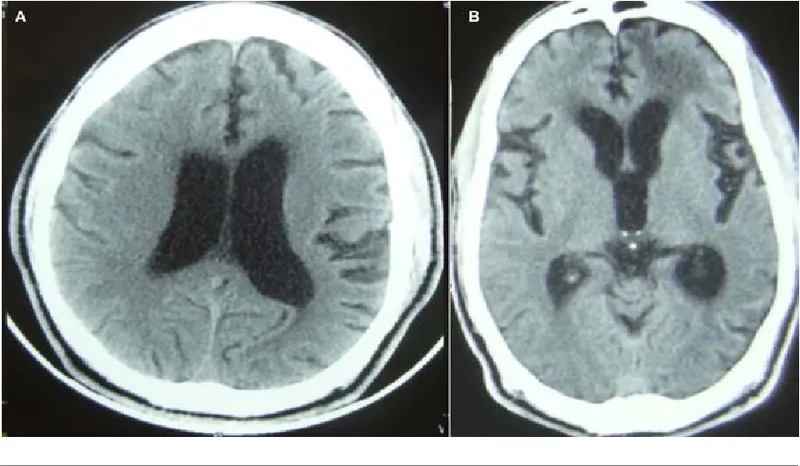

MRI brain scan showing enlarged ventricles in NPH

Understanding hydrocephalus in adults